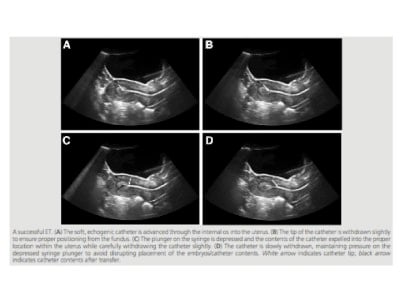

Embryo transfer is arguably the most critical step in the IVF process. On the surface, it seems like a relatively simple procedure. The embryos are loaded in a catheter and the physician deposits them through the cervical canal into the uterine cavity. It takes only a few minutes and is usually done with the patient wide awake, often with the partner right next to her.

There are two types of catheters available: soft and stiff. It has now been conclusively shown that soft catheters have higher success rates when compared to stiff catheters. Soft catheters are believed to follow the contour of the uterine cavity more easily and thereby result in less risk of plugging the tip with blood, mucus or the uterine lining causing less “trauma” or disruption of the lining. A stylette or a stiff catheter can be used to get through the cervical canal. It is important that the tip not be advanced beyond the cervical canal (internal os). The obturator is then removed and the embryos that are loaded in a soft catheter (noodle) are passed through the central channel of the stylette into the uterine cavity.